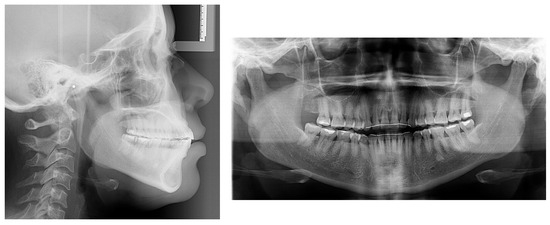

3. Treatment Results

4. Discussion

| Measurement | A (Initial) | B (Final) | Difference (A-B) |

|---|---|---|---|

| SNA° | 89.6 | 89.3 | 0.3 |

| SNB° | 84.7 | 84.6 | 0.1 |

| ANB° | 4.9 | 4.7 | 0.2 |

| SN-MP° | 38.7 | 37.5 | 1.2 |

| FMA° | 26.3 | 25.3 | 1.0 |

| UI TO NA mm | 6.8 | 5.7 | 1.1 |

| UI TO SN° | 119.6 | 115.1 | 4.5 |

| LI TO NB mm | 11.0 | 10.5 | 0.5 |

| LI TO MP° | 97.8 | 96.0 | 1.8 |

| U Lip to E-Line | −1.3 | −1.3 | 0.0 |

| L Lip to E-Line | 2.7 | 2.5 | 0.2 |